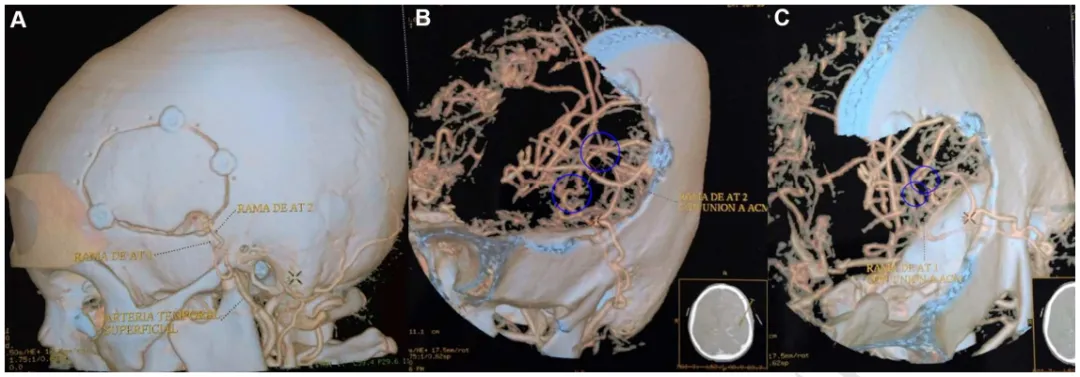

B&C:浩浩术前影像

浩浩术后CTA的3D重建显示开颅手术范围,以及在左侧颞浅动脉和左侧大脑中动脉之间进行的两次搭桥血管重建。